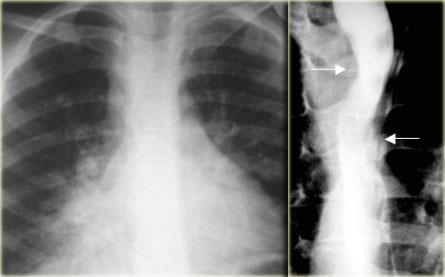

Quai động mạch chủ đôi (Double Arch)

Quai động mạch chủ đôi thường biểu hiện bằng tắc nghẽn đường thở, khó nuốt và hít sặc ở trẻ em.

Các quai ấn lõm thực quản ở các mức độ khác nhau.

Bên trái là một trường hợp quai động mạch chủ đôi khác.

Phim X-quang ngực cho thấy đông đặc phổi phải do hít sặc ở trẻ 6 tuổi.

Quai phải và quai trái ấn lõm thực quản (mũi tên) ở các mức độ khác nhau.